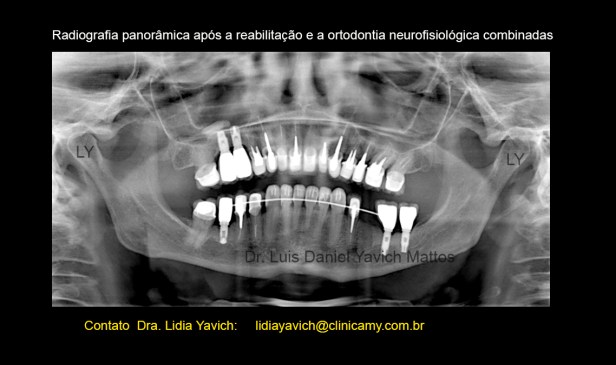

Ao exame radiográfico obseva-se ausência dos elementos dentais 18,16,28,28,36, 46 4 48.

Os elementos 15, 14, 22, 24, 26, 35,44 e 45 se encontram endodonticamente tratados.

Presença de prótese fixa com apoio nos elementos 16/15. Presença de prótese fixa unitária com pino metálico intracanal nos elementos 14, 22, 26, 35,34 e 45.

Extensa restauração coronária nos elementos 13,24 e 44.

Presença de material restaurador nos elementos 11, 21, 23, 27,32 e 47.

Perda óssea alveolar na maxila e na mandíbula mais acentuada nas áreas edêntulas.

Alongamento do processo estiloide esquerdo.

Radiografias panorâmicas comparativas: inicial antes do tratamento em oclusão habitual e a panorâmica com os implantes colocados, com o DIO, dispositivo intraoral em posição neuromuscular fisiológica instalado em boca.

Radiografia panorâmica com a finalização da reabilitação e o espaço do dente 35 preservado para futuro implante.

Comparação das radiografias panorâmicas pré, durante e após a reabilitação neuromuscular fisiológica combinada com a ortodontia tridimensional.